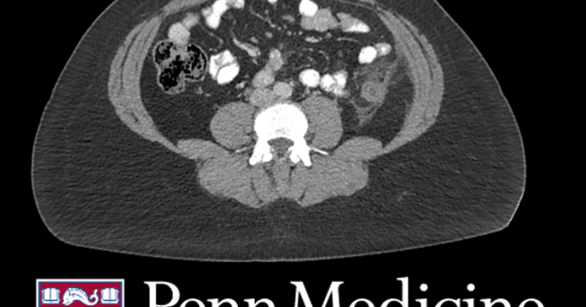

A 34-year-old woman presented to the clinic with several days of acute left lower quadrant abdominal pain without other significant symptoms. Can you solve this #radiology case from @PennRadiology?👇 https://t.co/JEIvuNLu5V

A 34-year-old woman presented to the clinic with several days of acute left lower quadrant abdominal pain without other significant symptoms. Can you solve this #radiology case from Dr. Richard Wu? https://t.co/w4N40ER48T

A 34-year-old woman presented to the clinic with several days of acute left lower quadrant abdominal pain without other significant symptoms.